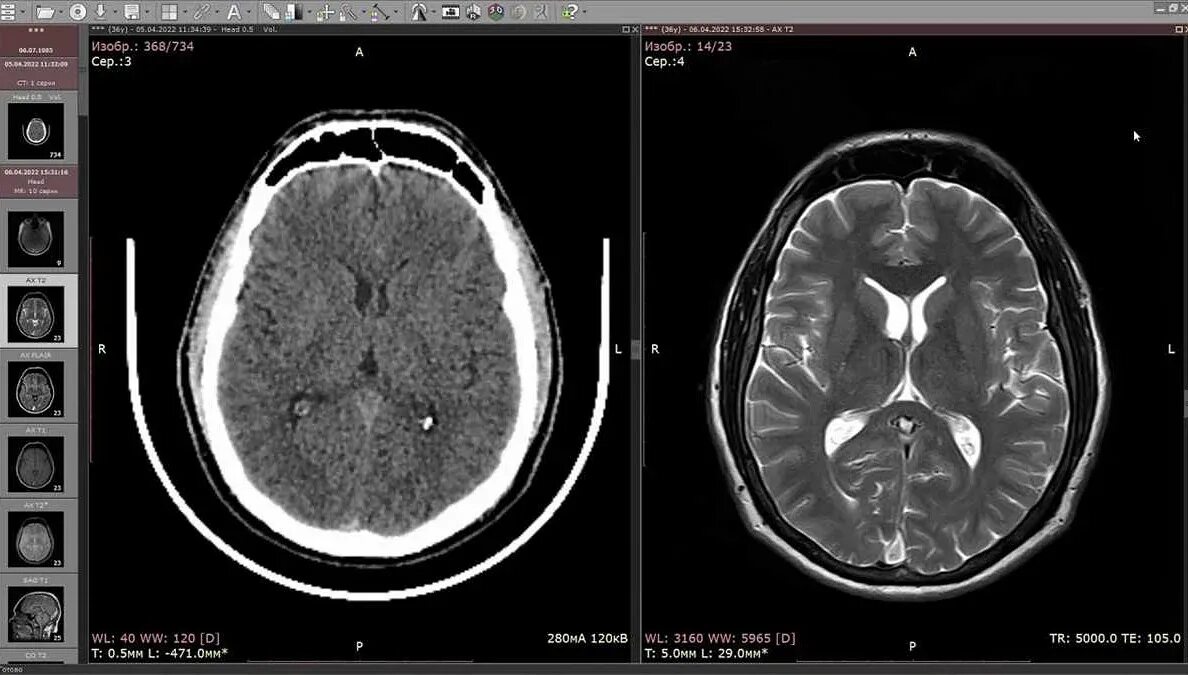

Чем отличается кт от мрт головы